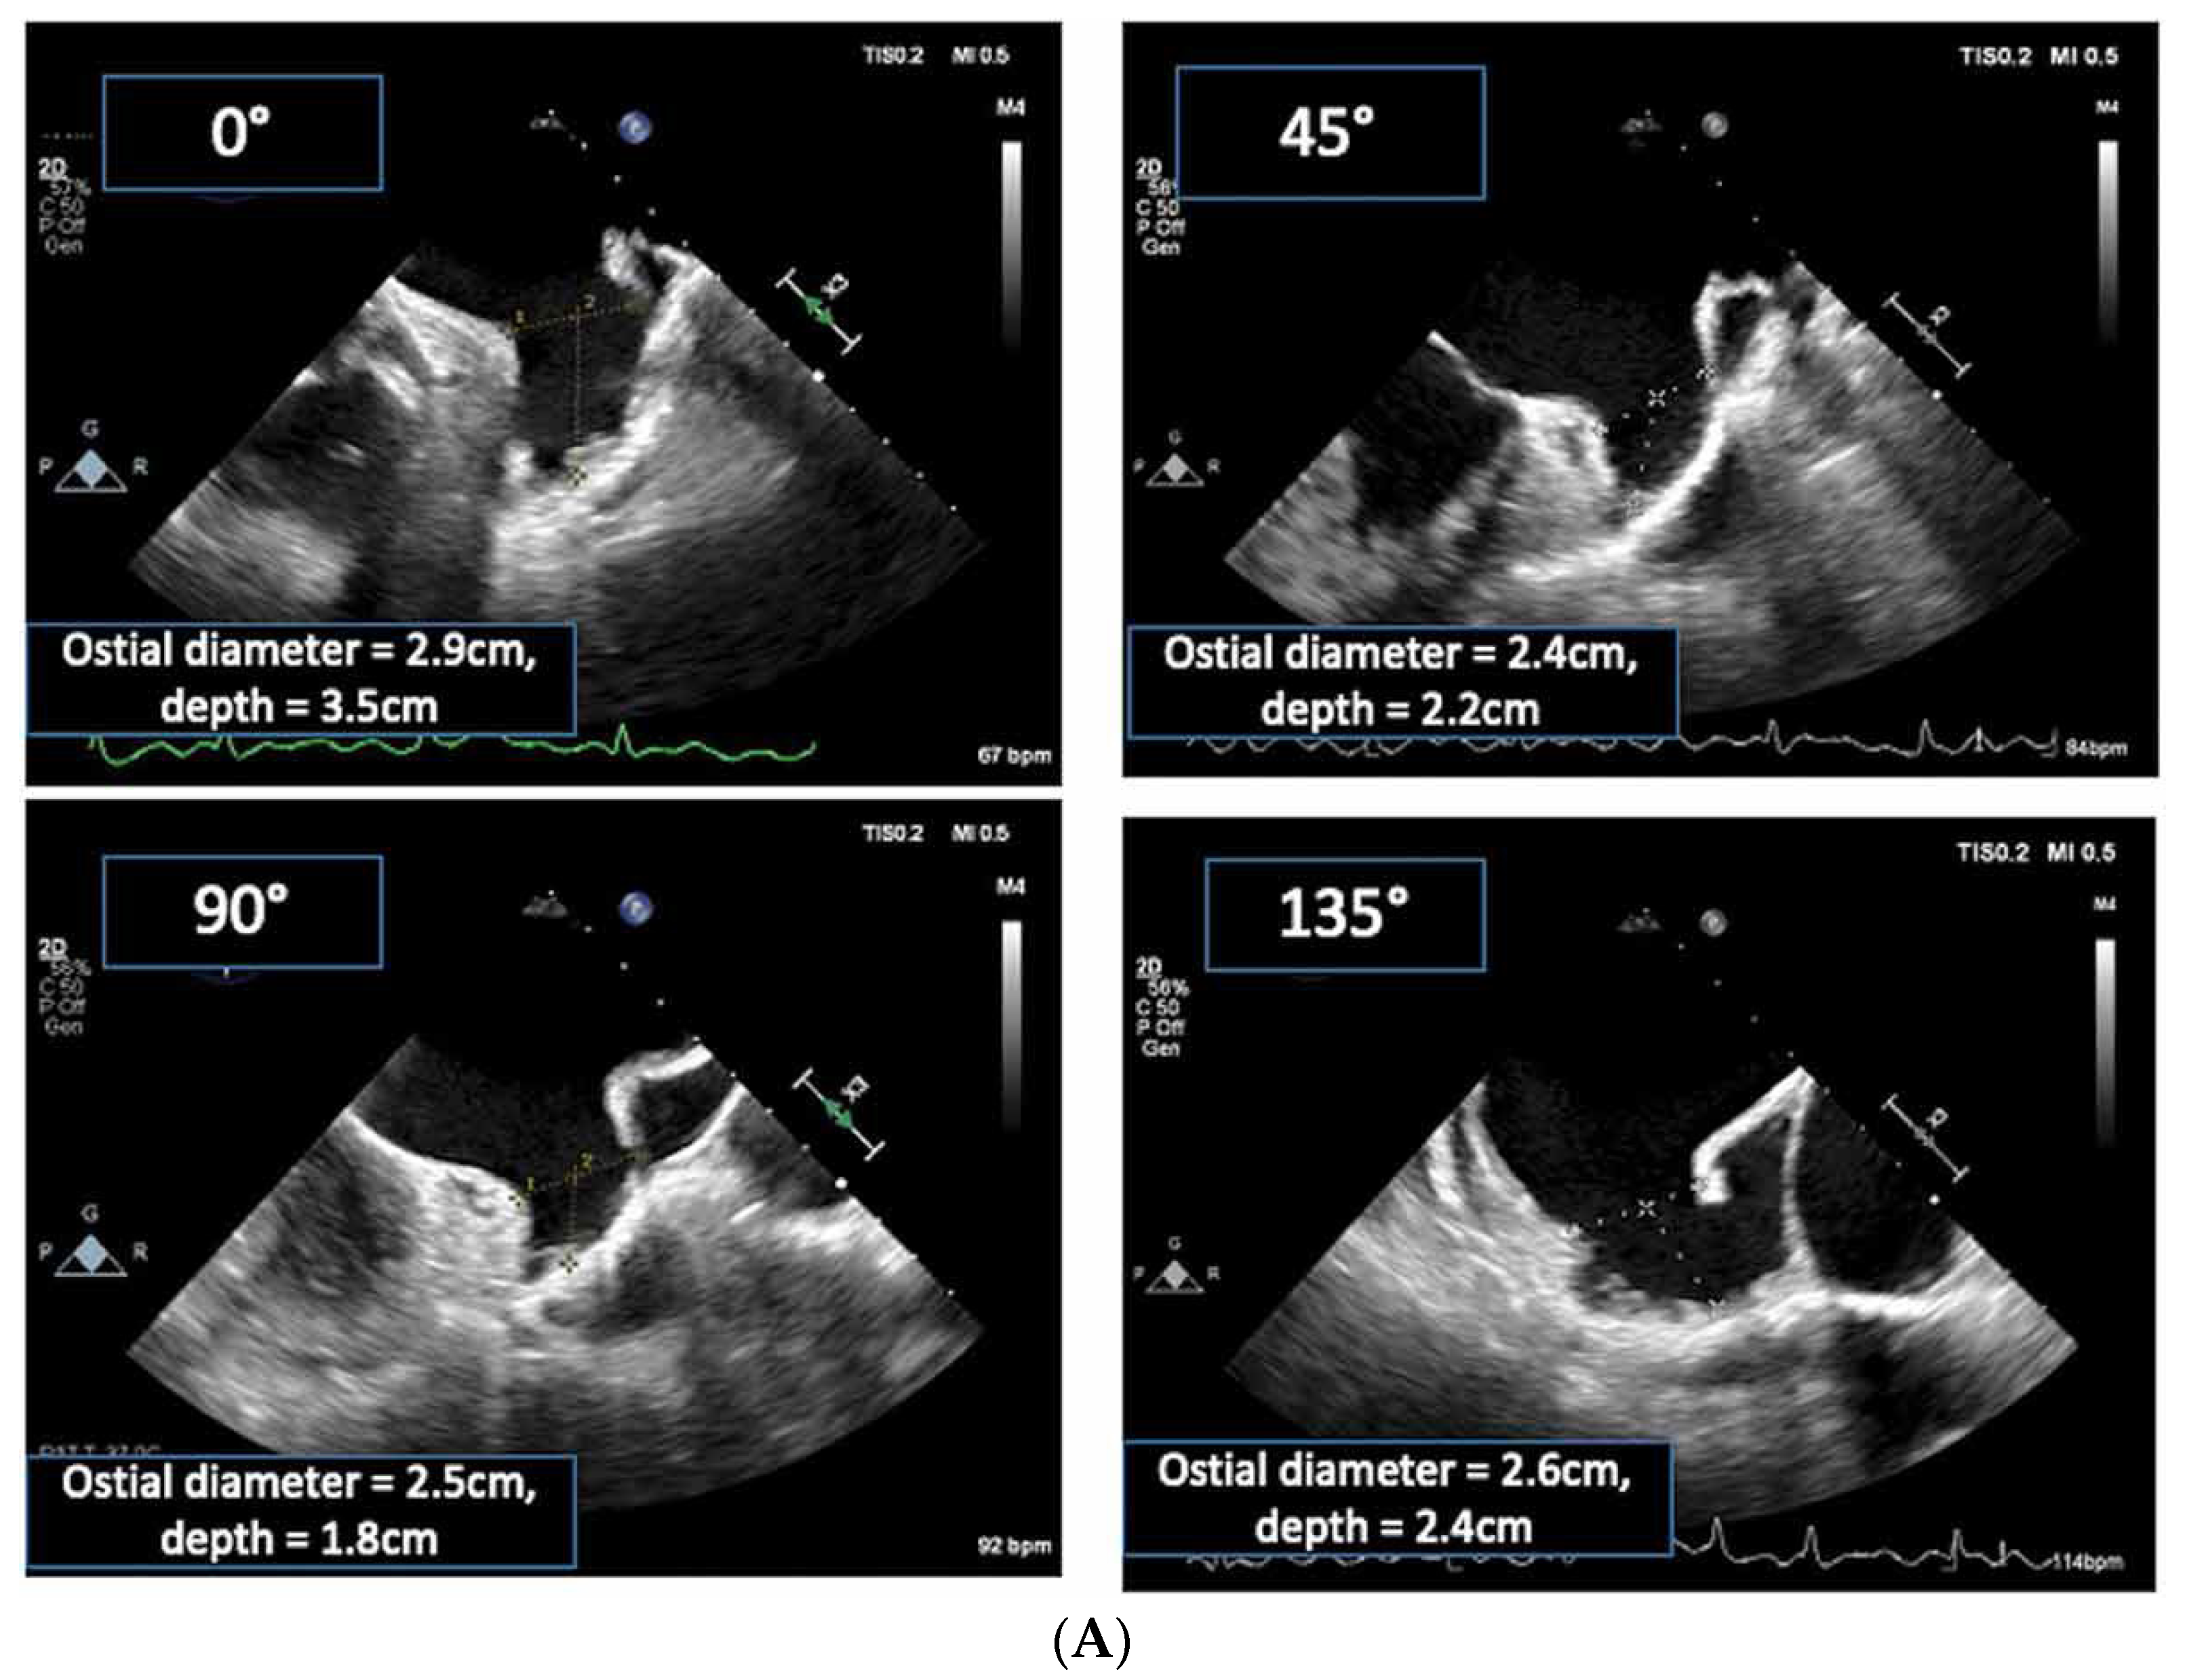

2.2.2. LAA Measurements (Anatomy and Morphology)

2.2.3. Intra-Procedural TOE